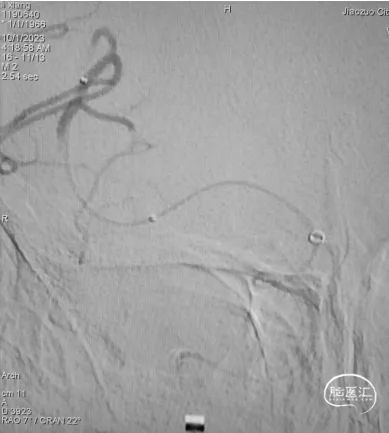

DSA提示:右侧大脑中动脉M1段以远闭塞,右侧大脑前动脉皮层支少量代偿,右侧大脑前动脉A3段血栓影,远端流速可,基底动脉尖端未见显影,考虑急性闭塞。

6F心玮吞川®颅内血栓抽吸导管同轴配合8F心玮天梯®支撑导管在泥鳅导丝导引下放置于右侧颈内动脉眼段。

微导丝配合微导管沿颅内血栓抽吸导管小心通过右侧大脑中动脉血栓段,微导管造影示右侧大脑中动脉远端血流通畅。

确定血栓长度后,以4.0*30mm颅内取栓支架行右侧大脑中动脉取栓配合中间导管抽吸。

造影提示右侧大脑中动脉血流通畅。